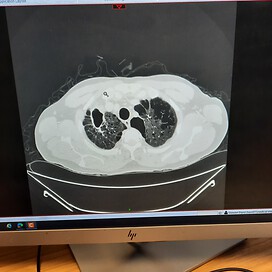

My main worry right now is trying to fully understand this new diagnosis as on a recent chest x-ray It showed i have a shadow on the upper part of my right

lung, upon a further CT scan it's now been confirmed as severe emphysema and my lung capacity is around 35 to 40%.